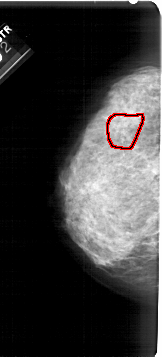

A_1939_1.LEFT_CC

LEFT_CC LINES 5341 PIXELS_PER_LINE 2416 BITS_PER_PIXEL 12 RESOLUTION 43.5 OVERLAY

FILE: A_1939_1.LEFT_MLO.OVERLAY

TOTAL_ABNORMALITIES 1

ABNORMALITY 1

LESION_TYPE CALCIFICATION TYPE AMORPHOUS DISTRIBUTION SEGMENTAL

ASSESSMENT 4

SUBTLETY 3

PATHOLOGY BENIGN

TOTAL_OUTLINES 1

BOUNDARY